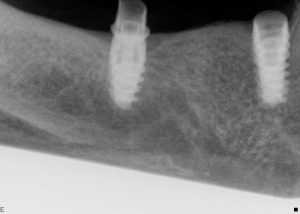

Implants have been around since 1965 and were originally used...